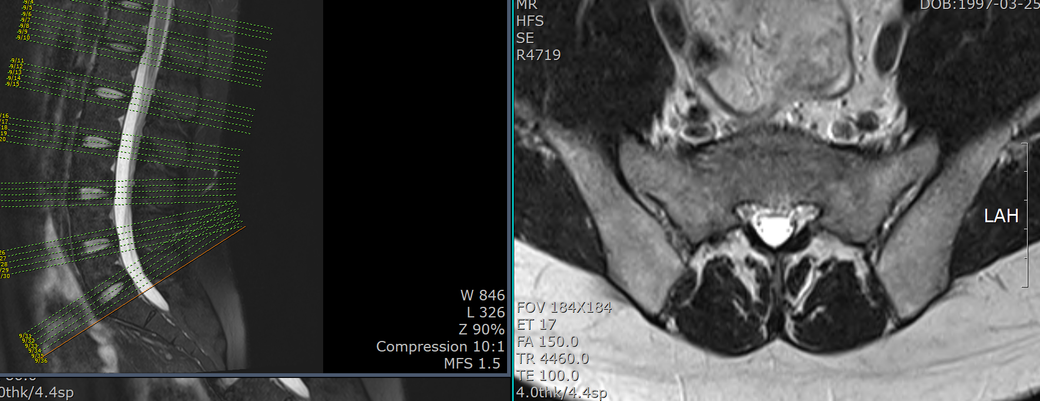

T12-L1 level에서 disc가 뒤쪽 Lt. central aspect로 protrusion되어 있고 mild한 dural sac indentation을 주고 있음.

< Sagittal whole spine T2WI image >

C4-5, C5-6 disc herniation at sagittal whole spine T2WI image

• 2번 째 사진

아래 사진에 있는 부위가 아마 T12/L1 사이에 디스크가 살짝 뒤로 빠져있다는 부위이실겁니다.

옆에서 보면 두번째 사진이구요.

우선은 이 디스크 내장증으로 인한 연관통으로 보고 요추전만 자세를 잘 실천해보시는게 가장 우선 필요한 조치이겠습니다.

수술을 주로 다루는 신경외과, 정형외과 선생님들의 경우에 심한 디스크탈출 및 신경뿌리를 누르는 신경뿌리병증이 생길만한 병변만 통증을 유발한다고 보시기 때문에 문제될만한 병변이 없다고 이야기 하셨을텐데 저렇게 작게 찢어진 디스크 때문에도 충분히 통증이 생길 수 있습니다. 물론 찢어진 디스크의 위치에 비해 통증이 밑에 있는 편이시지만 이게 불가능한건 아닙니다. 디스크 내장증이라고 하며 이럴때는 요추전만 자세가 가장 중요합니다.